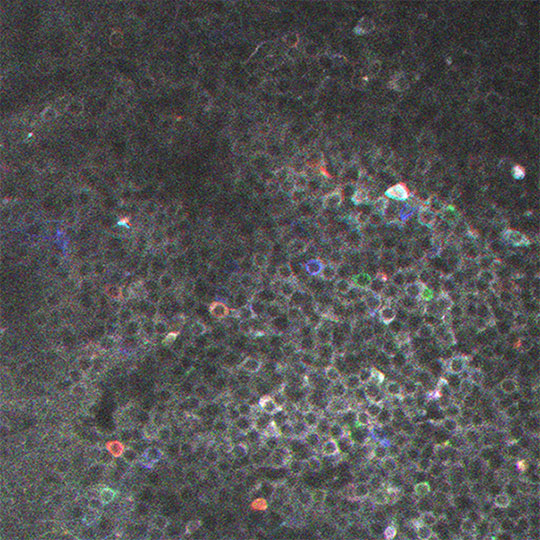

Figure: Neurones de la région CA1 de l'hippocampe visualisés en imagerie biphotonique et exprimant une protéine (GCaMP6) dont la fluorescence est sensible aux variations intracellulaires de calcium. Les couleurs indiquent les différentes assemblées neuronales.

© Susanne Reichinnek

Il est maintenant possible de voir dans le cerveau d'une souris éveillée plusieurs milliers de neurones de l'hippocampe en action, grâce à l'imagerie calcium biphotonique. En étudiant l'activité neuronale lorsque la souris est immobile mais éveillée, l'équipe de Rosa Cossart démontre que les séquences d'activation neuronale observées au cours de l'expérience sont en réalité constituées "d'assemblées neuronales", activées les unes après les autres. Ce résultat permet ainsi de définir un nouvel élément dans le mécanisme de l'encodage de la mémoire: entre le neurone qui représente l'instant "t" et la séquence qui intègre une expérience globale, il y a "l'assemblée neuronale", qui porte un fragment d'expérience. Pendant les périodes de veille, ces fragments sont souvent activés indépendamment les uns des autres (d'où la notion d'orthogonalité) mais aussi parfois activés ensemble, ce qui permet probablement de consolider le fait qu'ils ont été associés dans le temps. Ces assemblées représentent donc les briques élémentaires, support de notre mémoire, et à partir desquelles l'expérience se construit. C'est un peu comme si l'hippocampe jouait des gammes de musique pendant l'expérience (les séquences d'activation neuronale) et rejouait les accords correspondants (les assemblées) pendant la veille calme pour rappeler ou consolider cette expérience. Il sera essentiel d'étudier le devenir de ces assemblées dans le cadre de maladies neurodégénératives, associées à des défauts de la mémoire, comme par exemple la maladie d'Alzheimer.